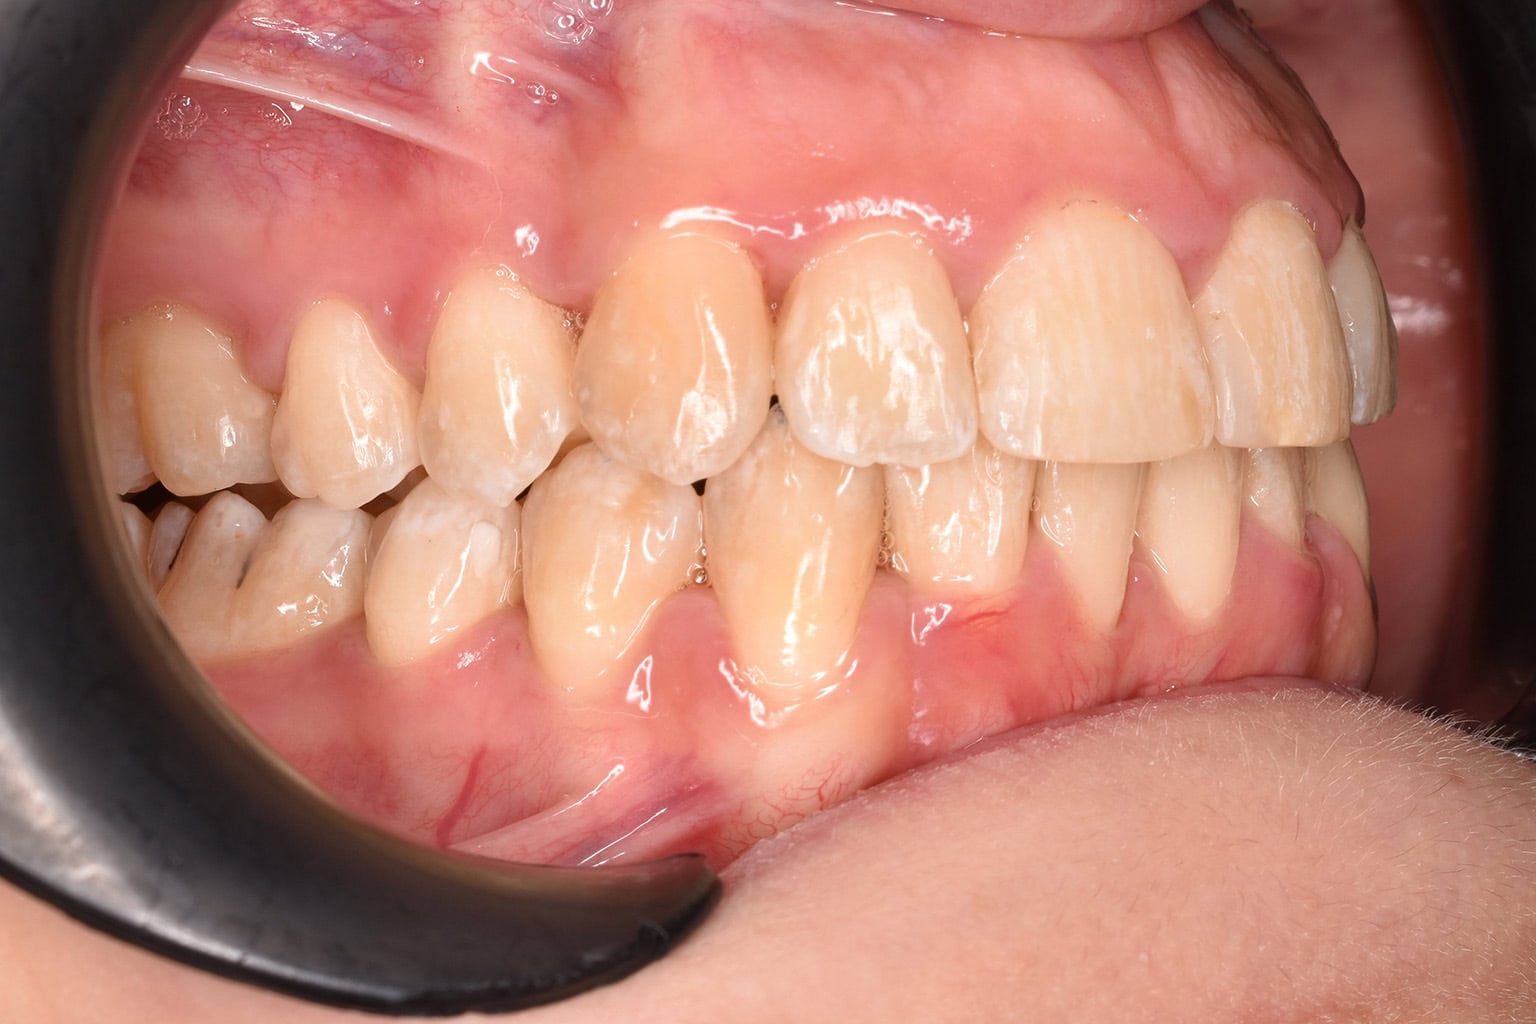

Vorher-Nachher-Ergebnisse

Echte Ergebnisse. Echte Menschen.

Jede Behandlung bei TIEFBLAU Kieferorthopädie ist so individuell wie der Mensch dahinter. In unserer Vorher-Nachher-Galerie zeigen wir Ihnen echte Behandlungsergebnisse aus unserer Praxis in der Kölner Südstadt: Schonend erzielt, präzise geplant und mit dem Anspruch, den wir seit über 40 Jahren an jede Behandlung stellen.

Die Bilder geben Ihnen einen Eindruck davon, was moderne Kieferorthopädie leisten kann, ob bei Kindern, Jugendlichen oder Erwachsenen.

Der sichtbare Unterschied

Dokumentiert. Überzeugend. Nachhaltig.